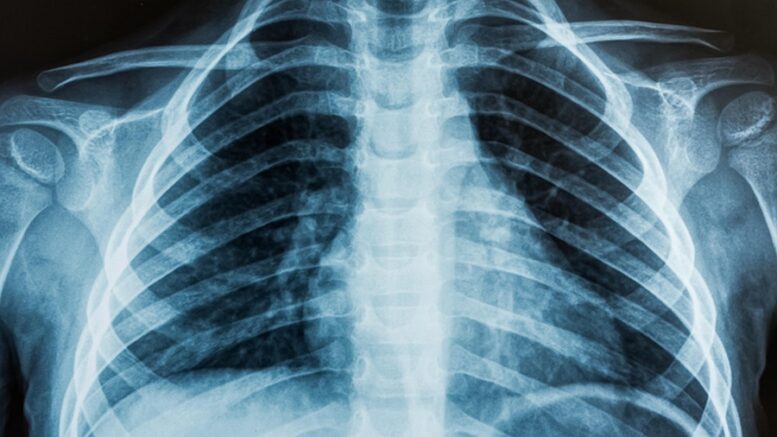

Diagnostic X-ray imaging was invented more than a century ago, but remains part of our daily lives – and an area ripe for innovation.

Most of us are aware that X-ray imaging is incredibly useful for diagnosing injury and disease. But it’s also dangerous – ionizing radiation can damage DNA and cause cancer.

So how do we know how much radiation we receive from X-ray machines, or from other sources? It starts with the amount of radiation produced by the source. X-rays are absorbed in our body differently by different kinds of tissue: Dense tissue, like bones, absorbs a lot of X-rays, while soft tissue absorbs less.

This is what creates the contrast in an X-ray image. Scientists have also developed models of human organs and tissue to account for the biological effect of radiation, measured in unites called sieverts.